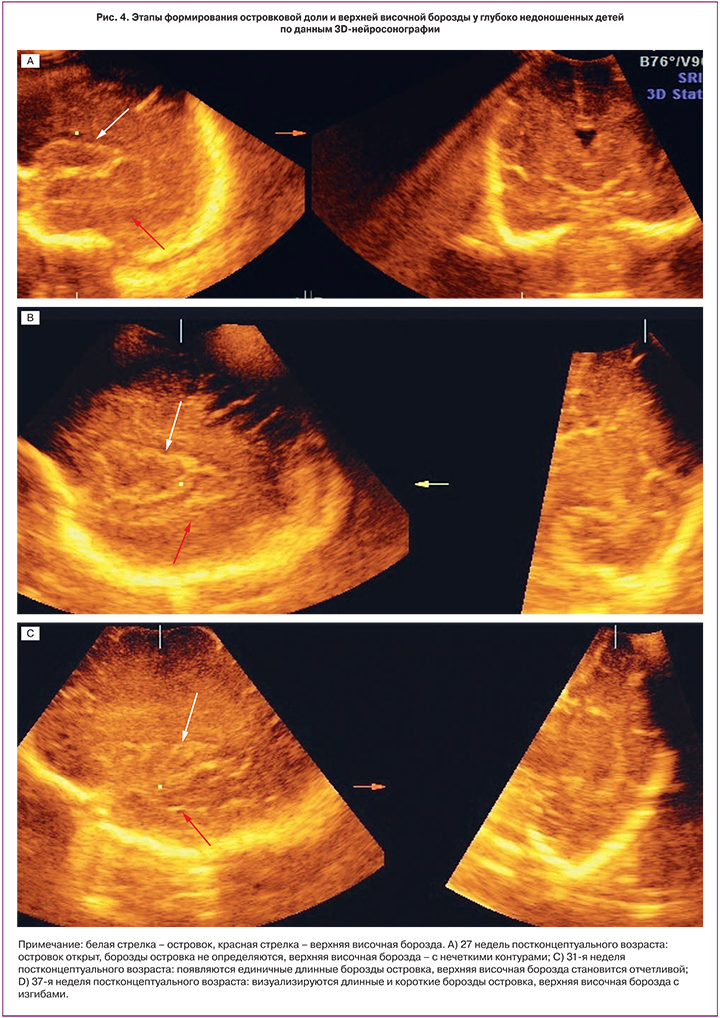

Закрытие островка мозга, по данным проведенного нами анализа, происходило в возрасте 31–32 недели; также в это же время начинали визуализироваться единичные длинные борозды островка, количество которых прогрессивно возрастало к 34-й неделе. Короткие борозды островка на сканограммах появлялись только после 34-й недели (рис. 4).

Верхняя височная борозда при исследовании в парасагиттальном срезе в сроке до 26–27 недель имела размытые прерывистые контуры, а с 28-й недели в большинстве случаев становилась отчетливой прямой линией, повторяющей задний контур островка. Формирование ее изгибов приходилось на возраст 34 недели (рис. 4).